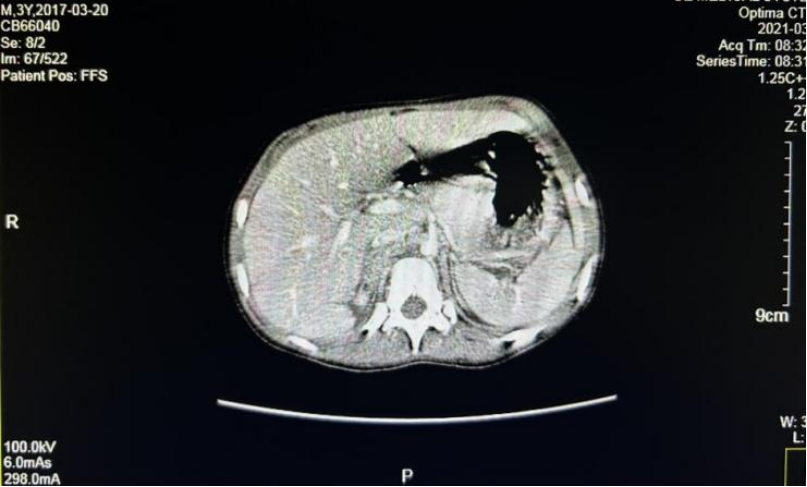

全腹部增强CT(2021.1.12)

右侧肾上腺区占位,范围约33.4 mm×50.2 mm×64.4 mm,考虑神经母细胞瘤伴多发骨转移;下腔静脉形态不规则,管壁稍毛糙,局部受侵犯可能;腹膜后多发肿大淋巴结。